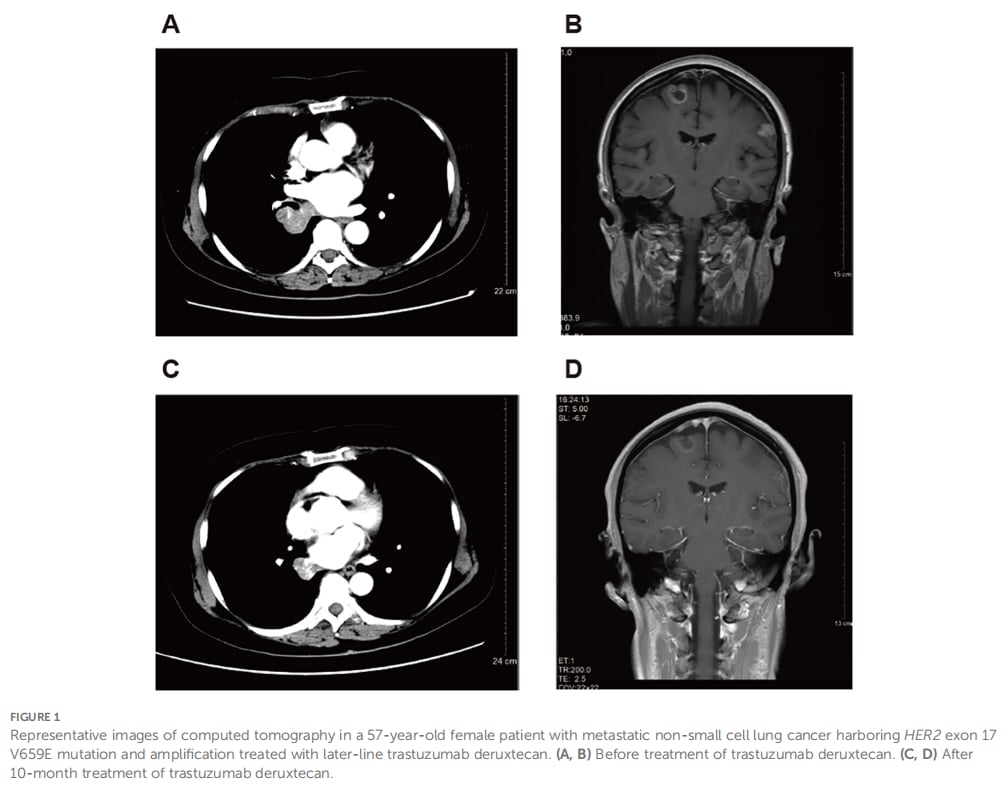

病例四:81岁高龄患者,PFS长达16个月

这位81岁高龄患者携带HER2 3外显子T126A突变,在一线接受德曲妥珠单抗治疗后,不仅达到了部分缓解,生活质量也从ECOG 3分显著改善至1分。其无进展生存期长达16个月后才出现疾病进展。这个案例表明,德曲妥珠单抗对于可能无法耐受标准化疗的老年患者,也是一个可行的优质选择。

▲ 图2 患者代表性CT影像